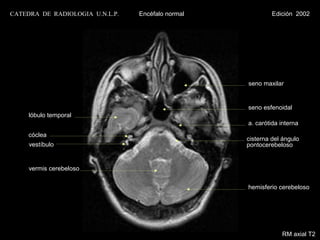

CATEDRA DE RADIOLOGIA U.N.L.P.   Encéfalo normal            Edición 2002

seno maxilar

seno esfenoidal

lóbulo temporal

a. carótida interna

cóclea

cisterna del ángulo

vestíbulo                                     pontocerebeloso

vermis cerebeloso

hemisferio cerebeloso

RM axial T2